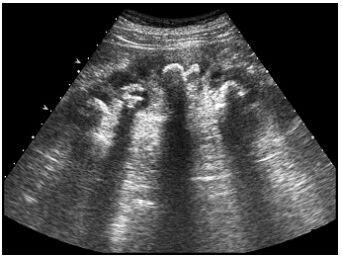

22.患者接受大腸鋇劑灌腸(barium enema)攝影的結果如下圖,最可能是下列何種疾病?(A)腸套疊 (B)惡性腫瘤 (C)腸扭轉 (D)腸炎